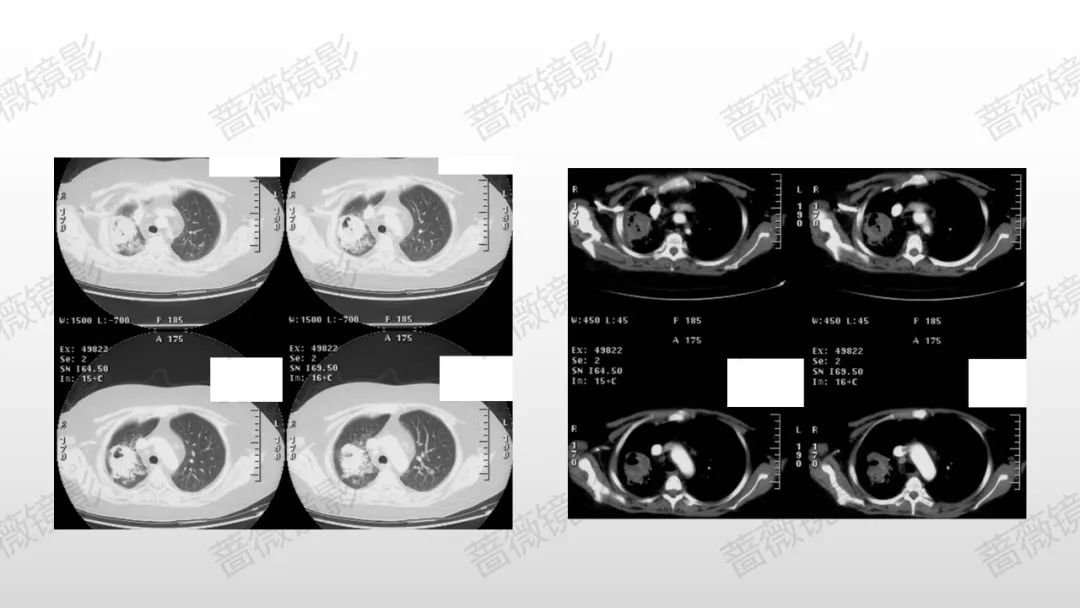

我对支气管肺泡灌洗液mNGS病原学检出的深层思考

虚拟导航引导超细内镜精准加压BAL能够解决什么问题?其短板如何弥补?